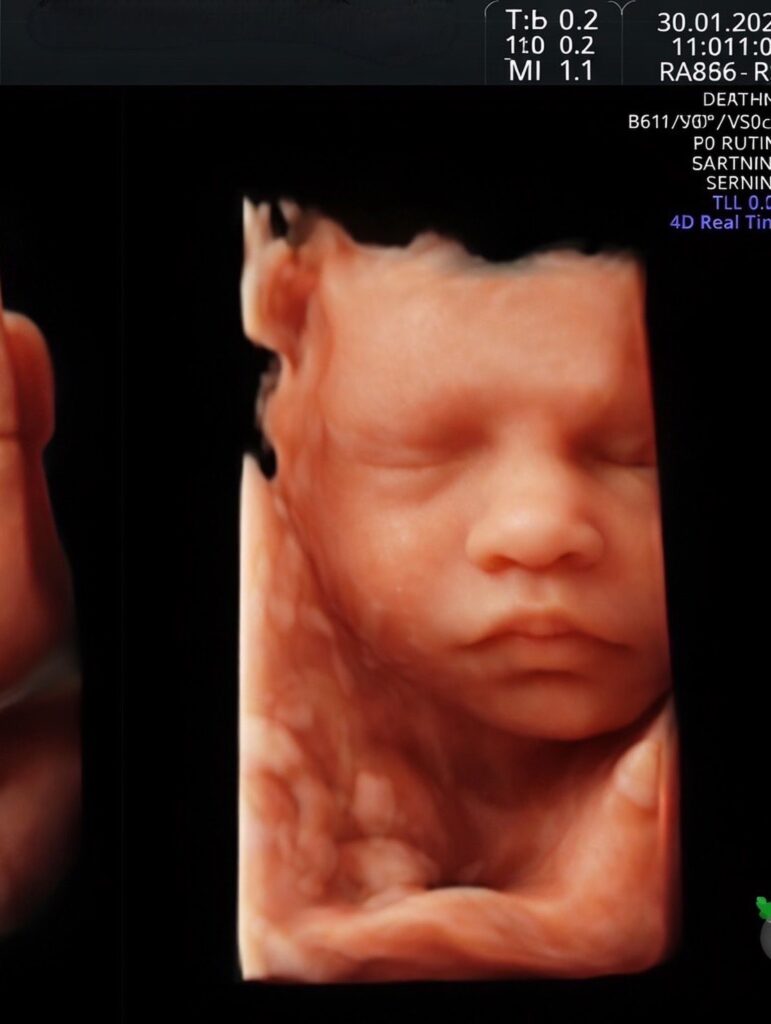

ซึ่งว่าที่คุณพ่อกอล์ฟ อนุวัฒน์ ก็ได้เปิดใจหลังว่าที่คุณแม่คนสวยคูณ ปิยวดี เข้ากระบวนการรักษาที่ GFC

กับแพทย์หญิง วรมา เกษมพิพัฒน์ชัย (คุณหมอวิว) เพียงครั้งเดียวติด ตอนนี้แพลนแพลนรับมือลูกคนแรกไว้แล้วว่า